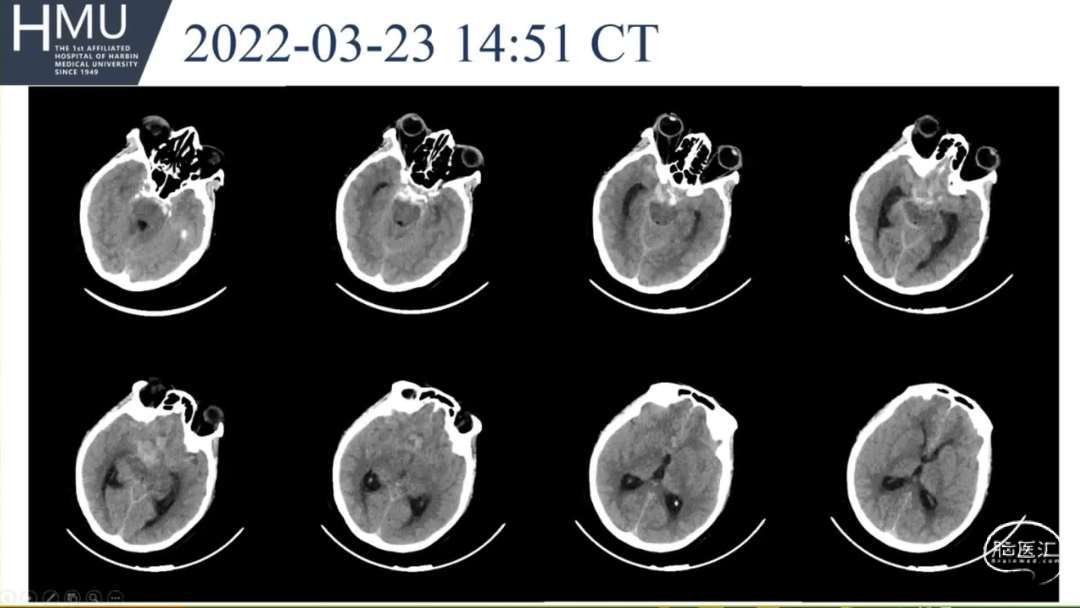

急行头部CT

23日14:00患者刺痛不睁眼,不发声,

右上肢刺痛定位,左侧瞳孔光反射消失。